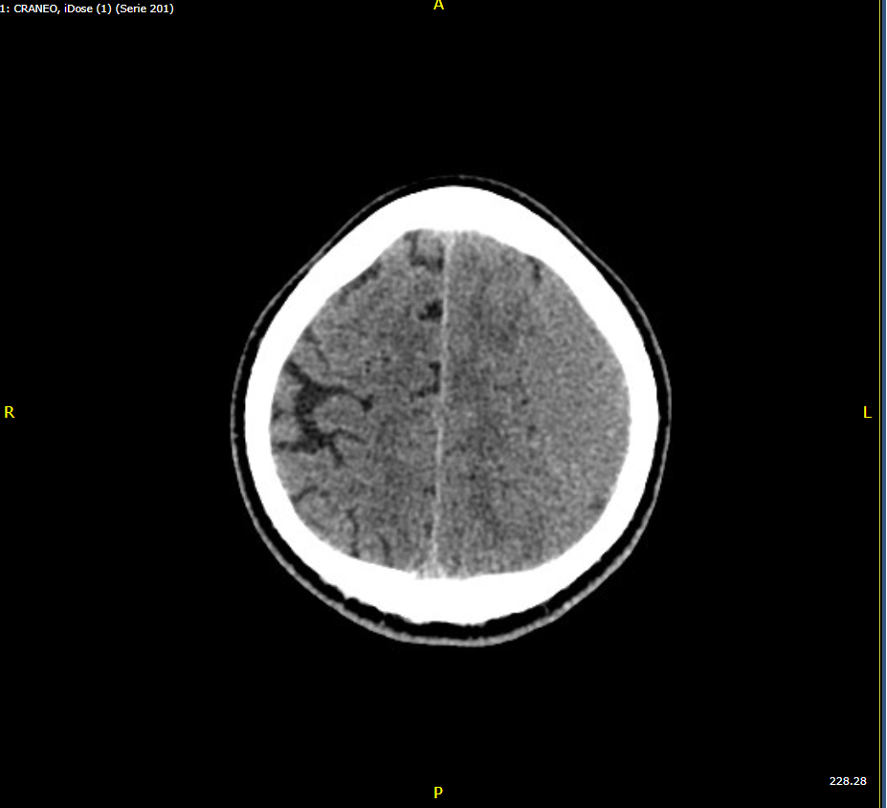

• TAC de cráneo: Hematoma subdural frontoparietal izdo, de probable evolución subaguda. Efecto de masa sobre parénquima cerebral, con obliteración de surcos de la convexidad izda, con mínimo desplazamiento de línea media (3 mm).

• Hematoma subdural frontoparietal izquierdo subagudo postraumático

Se comenta con el servicio de Neurocirugía consideran no patología quirúrgica urgente, indican ingreso vigilancia neurológica, profilaxis anticomicial y TAC de cráneo control en 72 horas.

Persiste colección hemática con puntos de resangrado. El paciente persiste pauci/asintomatico se plantea puede beneficiarse de embolización de meningea media.